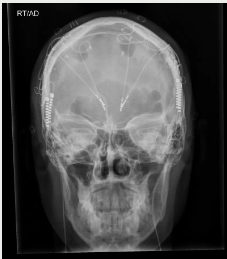

腦深部電刺激(DBS)使用電極激活神經(jīng)回路。在這張大腦的擴散張量圖像中,最亮的點表示植入物的位置

x射線圖像顯示了為治療抑郁癥而植入的兩根DBS電極。

DEPARTMENT OF NEUROSURGERY, BAYLOR COLLEGE OF MEDICINE